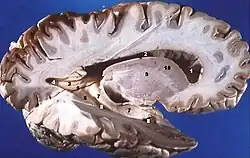

Dans l'encéphale, la substance grise est située en périphérie, c'est-à-dire autour de la substance blanche. De ce fait, on dit que la substance grise définit un cortex (« écorce » en latin). Ce cortex est formé d'un empilement de couches de cellules nerveuses (entre 3 et 6 pour le cortex cérébral et 3 pour le cortex cérébelleux) lesquelles se différencient par le type cytoarchitectonique, la densité cellulaire et la connectivité. Autour des ventricules cérébraux, la substance grise est agglutinée en amas cellulaires qui n'ont généralement pas l'organisation laminaire des cortex : ce sont les noyaux gris centraux (thalamus, ganglions de la base, etc.).

Au niveau du tronc cérébral, on retrouve aussi des noyaux de substance grise, notamment le tectum, le tegmentum, la substance grise périaqueducale ainsi qu'un certain nombre de noyaux des nerfs crâniens.

Au sein de la moelle spinale, la substance grise entoure le canal épendymaire et est donc circonscrite par la substance blanche en périphérie.